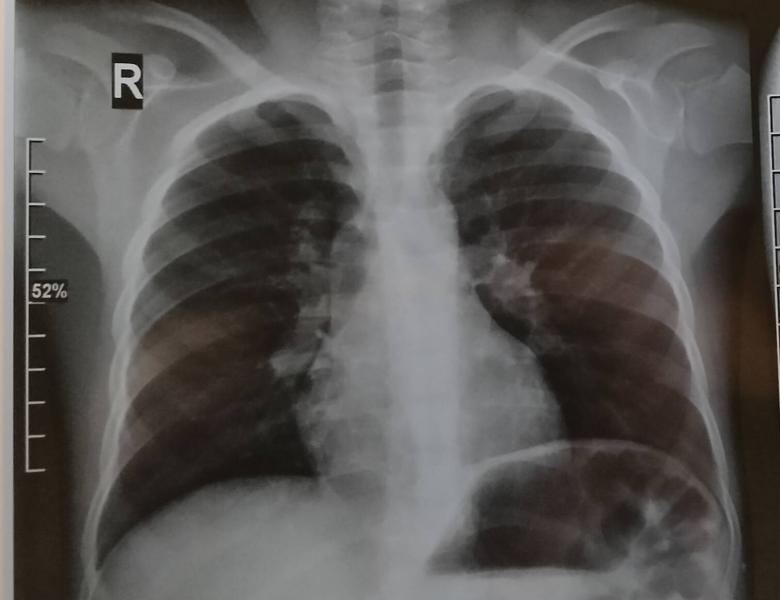

Но тут было другое. Из-за решения уйти под расписку до окончания лечения, Богдану решили повторить рентген (он как раз на картинке). Там увидели ателектаз верхней доли справа и... Предложили провести санационную бронхоскопию 🙈

Вчера (спустя неделю) мы сходили еще разок на рентген - динамика хорошая))

@mendelevna ого, пусть в следующем году, обойдет строной! А на снимках, мне кажется, все одинаково, как понять по снимку, что пневмония есть?